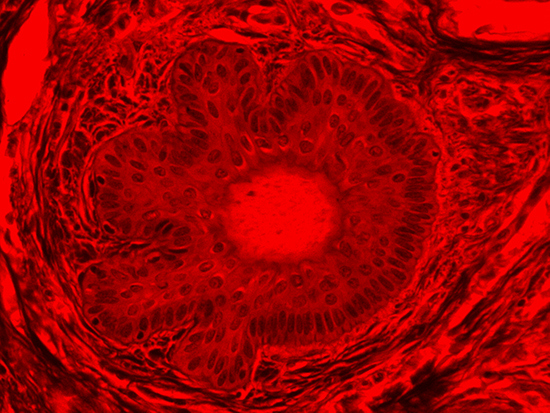

Figure 2: Darkfield Imaging of Dermal Tissue

When comparing Figures 1 and 2, the visual differences are significant. A brightfield image is formed with the illumination source below the sample, and then transmitted light propagates through the sample to the sensor forming a bright, white background with sharp color. A darkfield image is formed by directing light at an oblique angle through the sample, forming a hollow cone of light which is collected by the objective. Darkfield illumination typically yields a dark background with sharp color, but in the case of Figure 2, the collagen and muscle fibers interfered with the light path and caused a blur of light and color. The dark background is hardly evident and only two distinct colors are visible. When analyzing histological stains, brightfield illumination is the preferred technique for lighting a sample.

Figure 4: Brightfield Image of Dermal Tissue filtered with Red

When comparing Figure 3 with Figure 4, there is once again a significant visual difference. The most obvious feature is the change in color from green to red due to a different hardcoated filter being positioned in the optical path. The less obvious difference is the varying contrast levels caused by the filters at specific regions of the dermal tissue. For example, Figure 3 exhibits a distinct ring at the central region of the cell with additional matter within. In Figure 4, the ring is extremely faint and the internal matter is not visible. With that said, the cell and surrounding dense materials are more evident in Figure 3, whereas the muscle fibers and collagen are more pronounced in Figure 4.